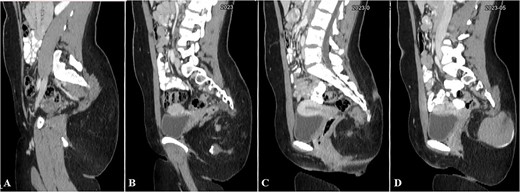

Contrast-enhanced computed tomography (CT) showed an ill-defined mass-like lesion in the gluteal region. The lesion consists of mixed tissue (fat predominantly, fluid and calcifications) and is seen exerting mass effect on the adjacent muscles and extending into the ischioanal, ischiorectal fossa and pre-coccygeal region (Figs 1 and 2).

Selected sagittal CT cuts of the pelvis with oral and IV contrast (Venous phase) from left to right sides of the body (A–D), showing the mentioned gluteal mass. The cystic component of the mass is noted at the right gluteal region and the pre-coccygeal portion is well shown in C.